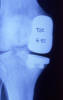

Densitometría en calcáneo